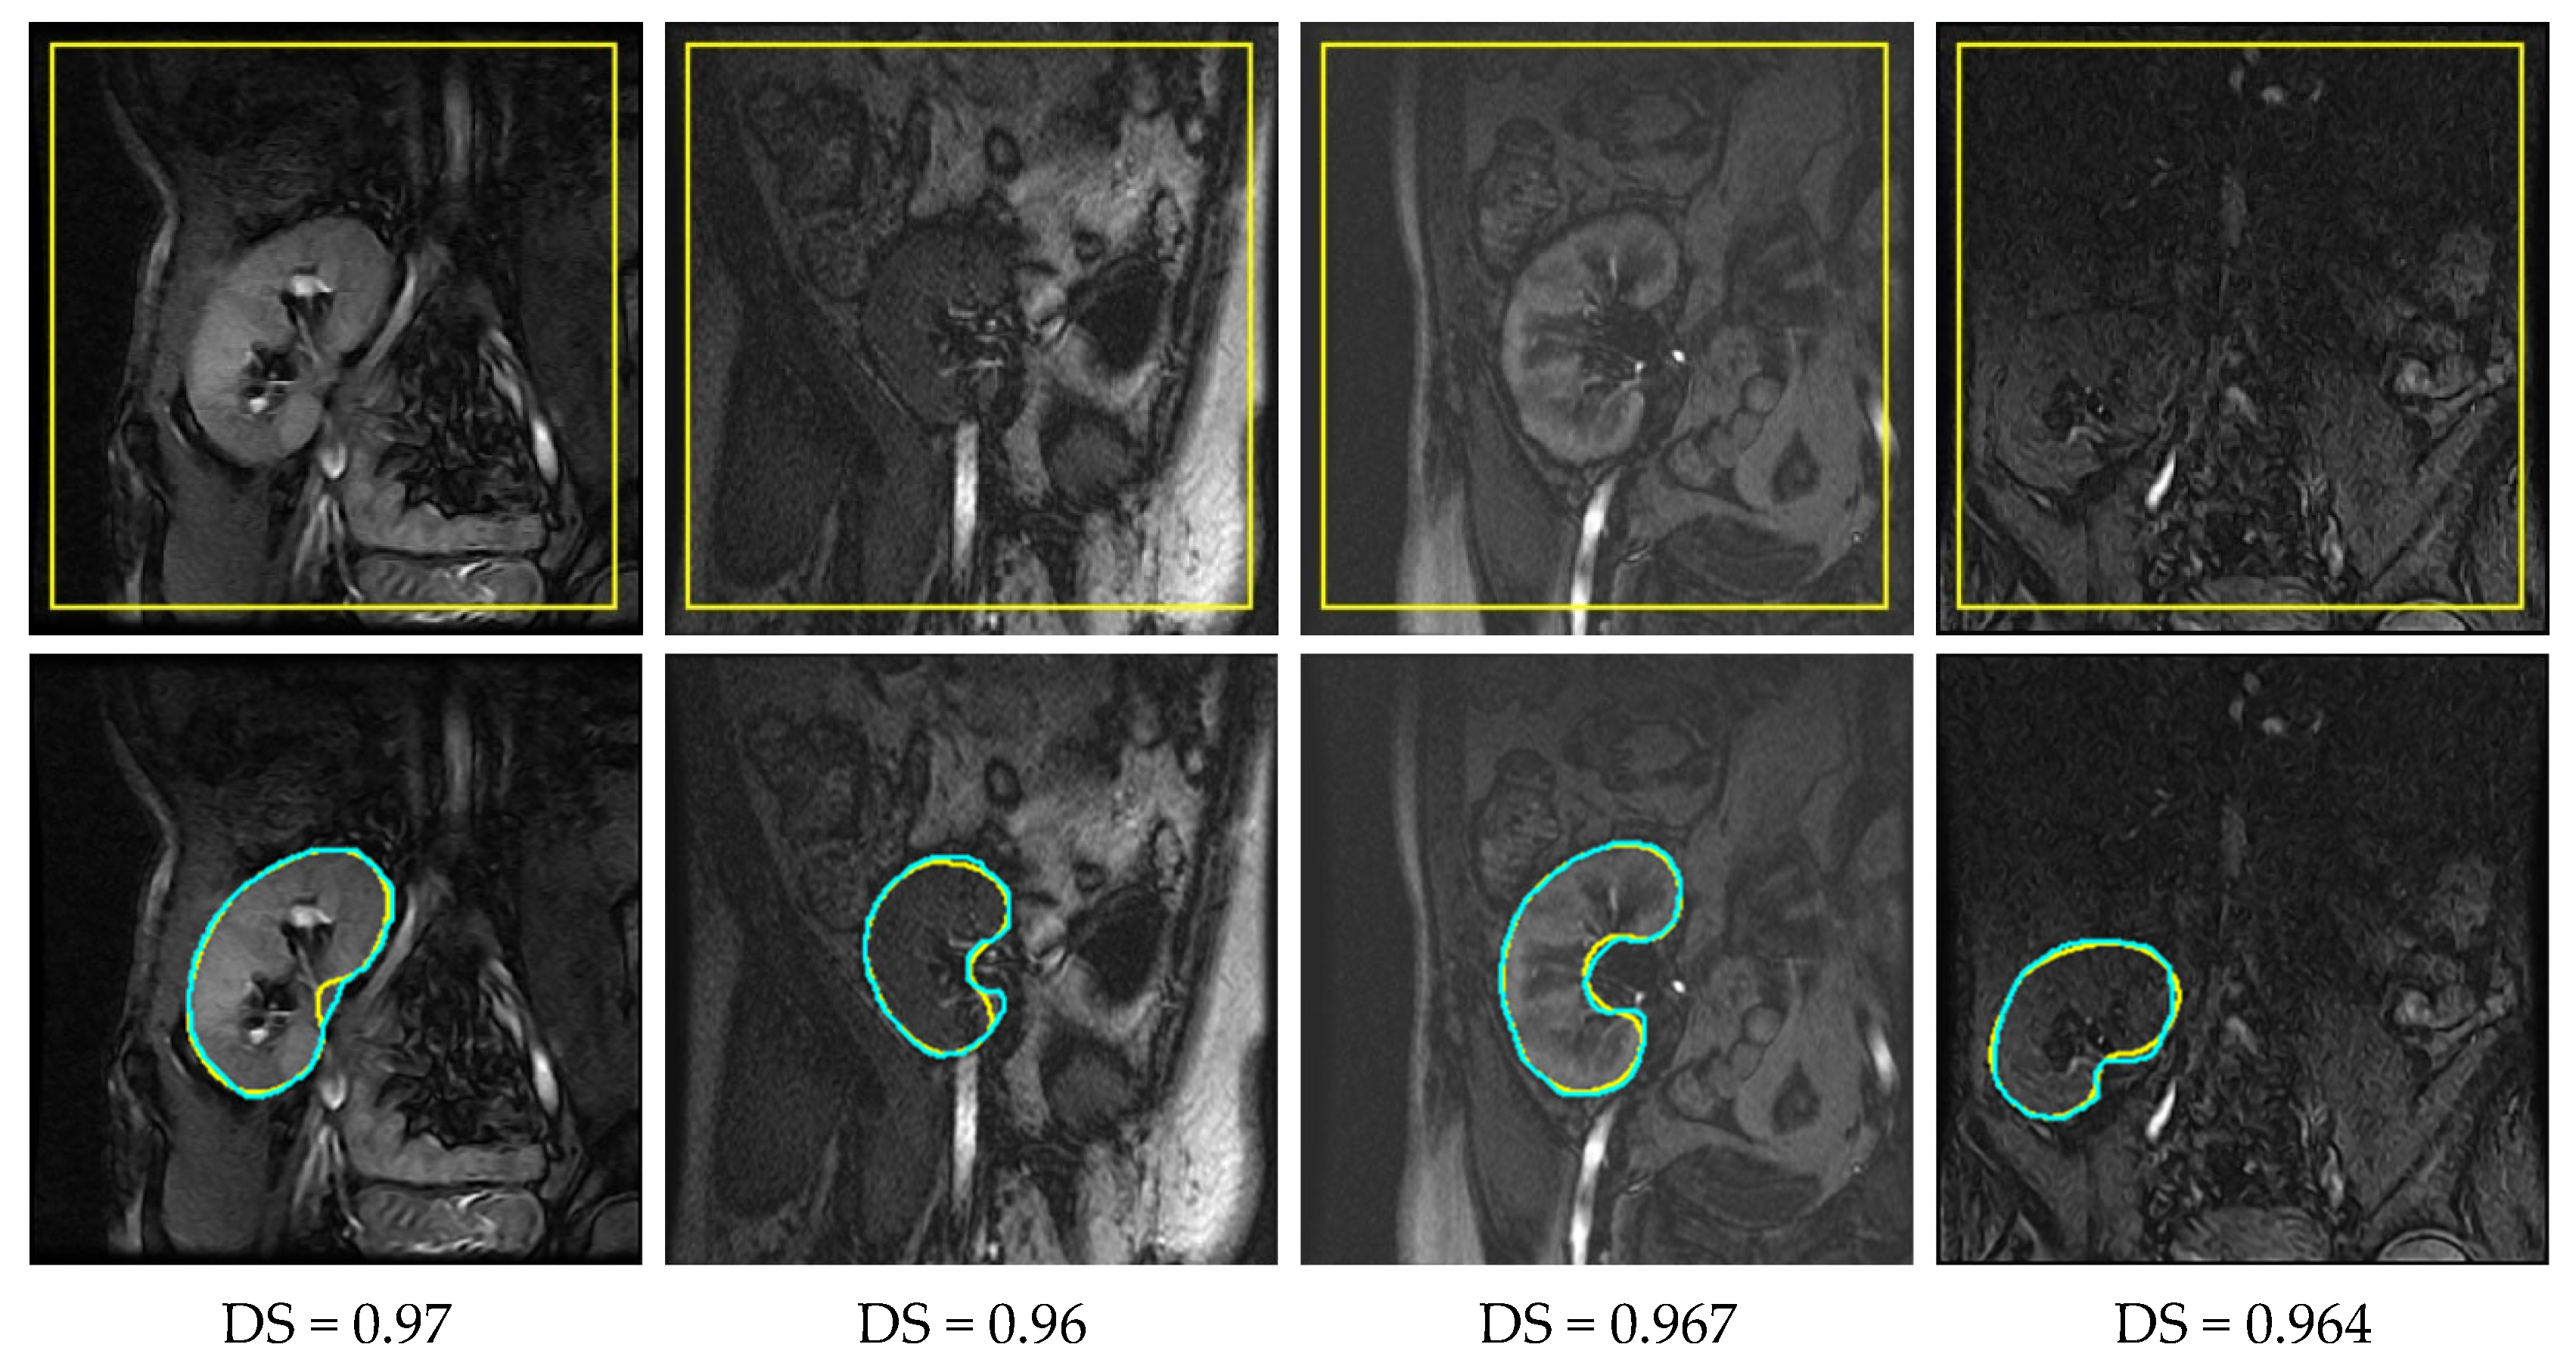

2.1. Data

3.2. Performance Evaluation

4.2. Results